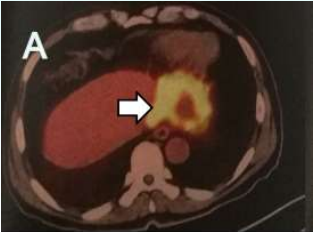

此前患者因無明顯誘因出現(xiàn)胃納下降,伴進(jìn)行性消瘦。外院CT檢查提示肝臟占位,后完善PET/CT檢查并行肝臟腫物穿刺活檢,病理提示:肝膽管細(xì)胞癌。

影像檢查

入院完善相關(guān)檢查發(fā)現(xiàn),其肝臟病灶與鄰近胃小彎、膈肌粘連、分界不清;門靜脈左支及肝左靜脈未見顯示,考慮受侵;左上腹腔前側(cè)及后側(cè)腹膜局限性增厚,考慮腹膜轉(zhuǎn)移瘤,部分病灶與鄰近左側(cè)膈肌、脾臟粘連、分界不清。

此外,腫瘤標(biāo)志物尤其是CA19-9:259.4U/ml,CA125:103.40U/ml。

以劉樹鵬副主任為首的醫(yī)療五科專家團(tuán)隊(duì)充分研討后認(rèn)為:該患者腫瘤位于肝膽管區(qū)域,大小約7.4cm*5.9cm*6.2cm,且腫瘤性質(zhì)明確,為肝膽管細(xì)胞癌。多學(xué)科會(huì)診后,考慮患者腫瘤已侵犯周圍組織,同時(shí)伴遠(yuǎn)處轉(zhuǎn)移癌,無手術(shù)切除指征,專家為其采用不可逆電穿孔消融(IRE)聯(lián)合化療方案治療。